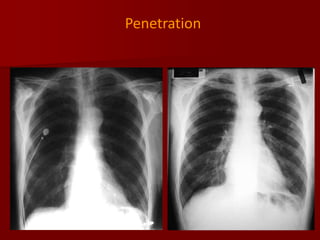

Penetration:

Refers to adequate photons traversing the patient to expose the

radiograph.

 The lack of penetration renders the area “whiter” than with an

adequate film and can simulate pneumonia or effusion.

 In an ideal radiograph the thoracic spine should be barely

perceptual viewing through the cardiac shadow , the left hemidiaphragm behind heart and vessels only up to 2/3 of lung area

In lateral view 2 sets of ribs should be seen, sternum seen,

spine appears clearer as it goes down.

Penetration